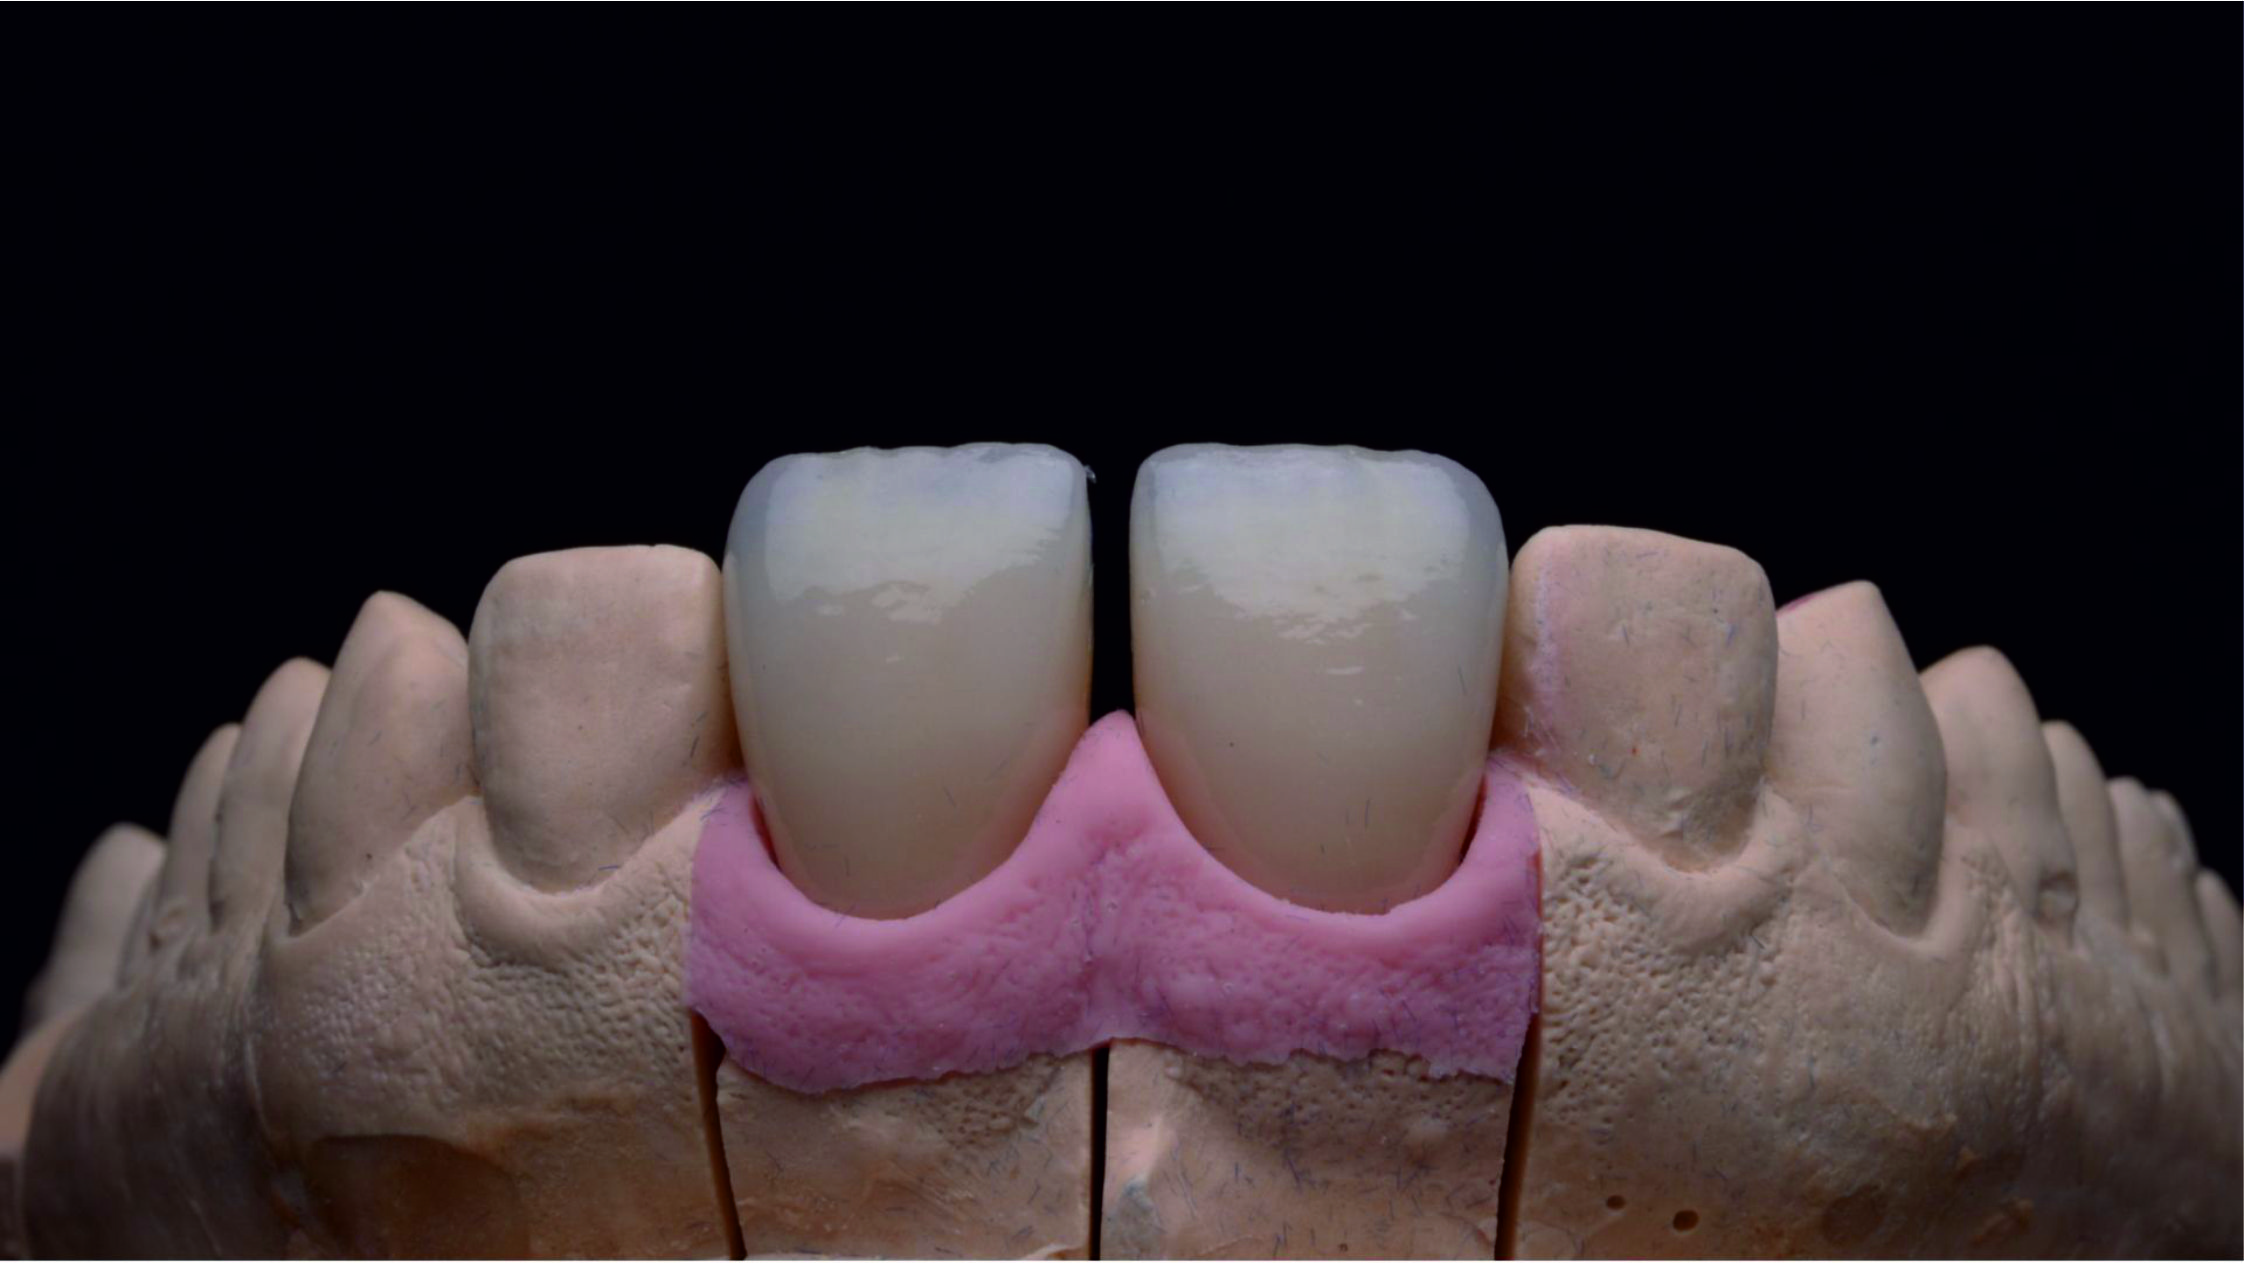

Фото 29. Виготовлені в лабораторії суцільнокерамічні реставрації з дисилікату літію.

Фото 30.

Фото 31. На етапі примірки ми перевірили реставрації щодо відповідності параметрів і форми, розрахованих нами за допомогою тимчасових конструкцій. Для цього ми встановили реставрації поруч одна з одною.